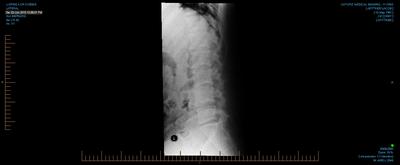

That worried the sports doctor so he sent me for lower spine and SI joint x-rays.

I apologize for the verbose letter, but writing it was rather therapeutic. I've attached my x-ray images and hope you can tell me what you see.

Clearly you've had a full prolapsed disc, almost certainly at the L5-S1 level. The change in the shape of the disc seen on the lateral xray explains your posture and the loss of the inward curve that concerned your sports doctor.

A scan would be useful, but the result is highly predictable; a large postero lateral bulge, possibly into the IVF. I know something of what you've been going through, because I've treated hundreds, perhaps thousands of similar cases, and been there myself, just at a higher level which affected the femoral nerve. The pain in the leg is unbelievable, so don't feel you're being a baby; it hurts big time.